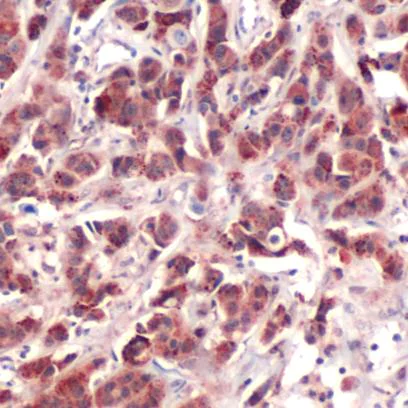

Immunohistochemistry (Formalin/PFA-fixed paraffin-embedded sections) - Anti-S6K1 antibody (AB227772)

Formalin-fixed, paraffin-embedded human breast carcinoma tissue stained for S6K1 using ab227772 at 1/50 dilution in immunohistochemical analysis.